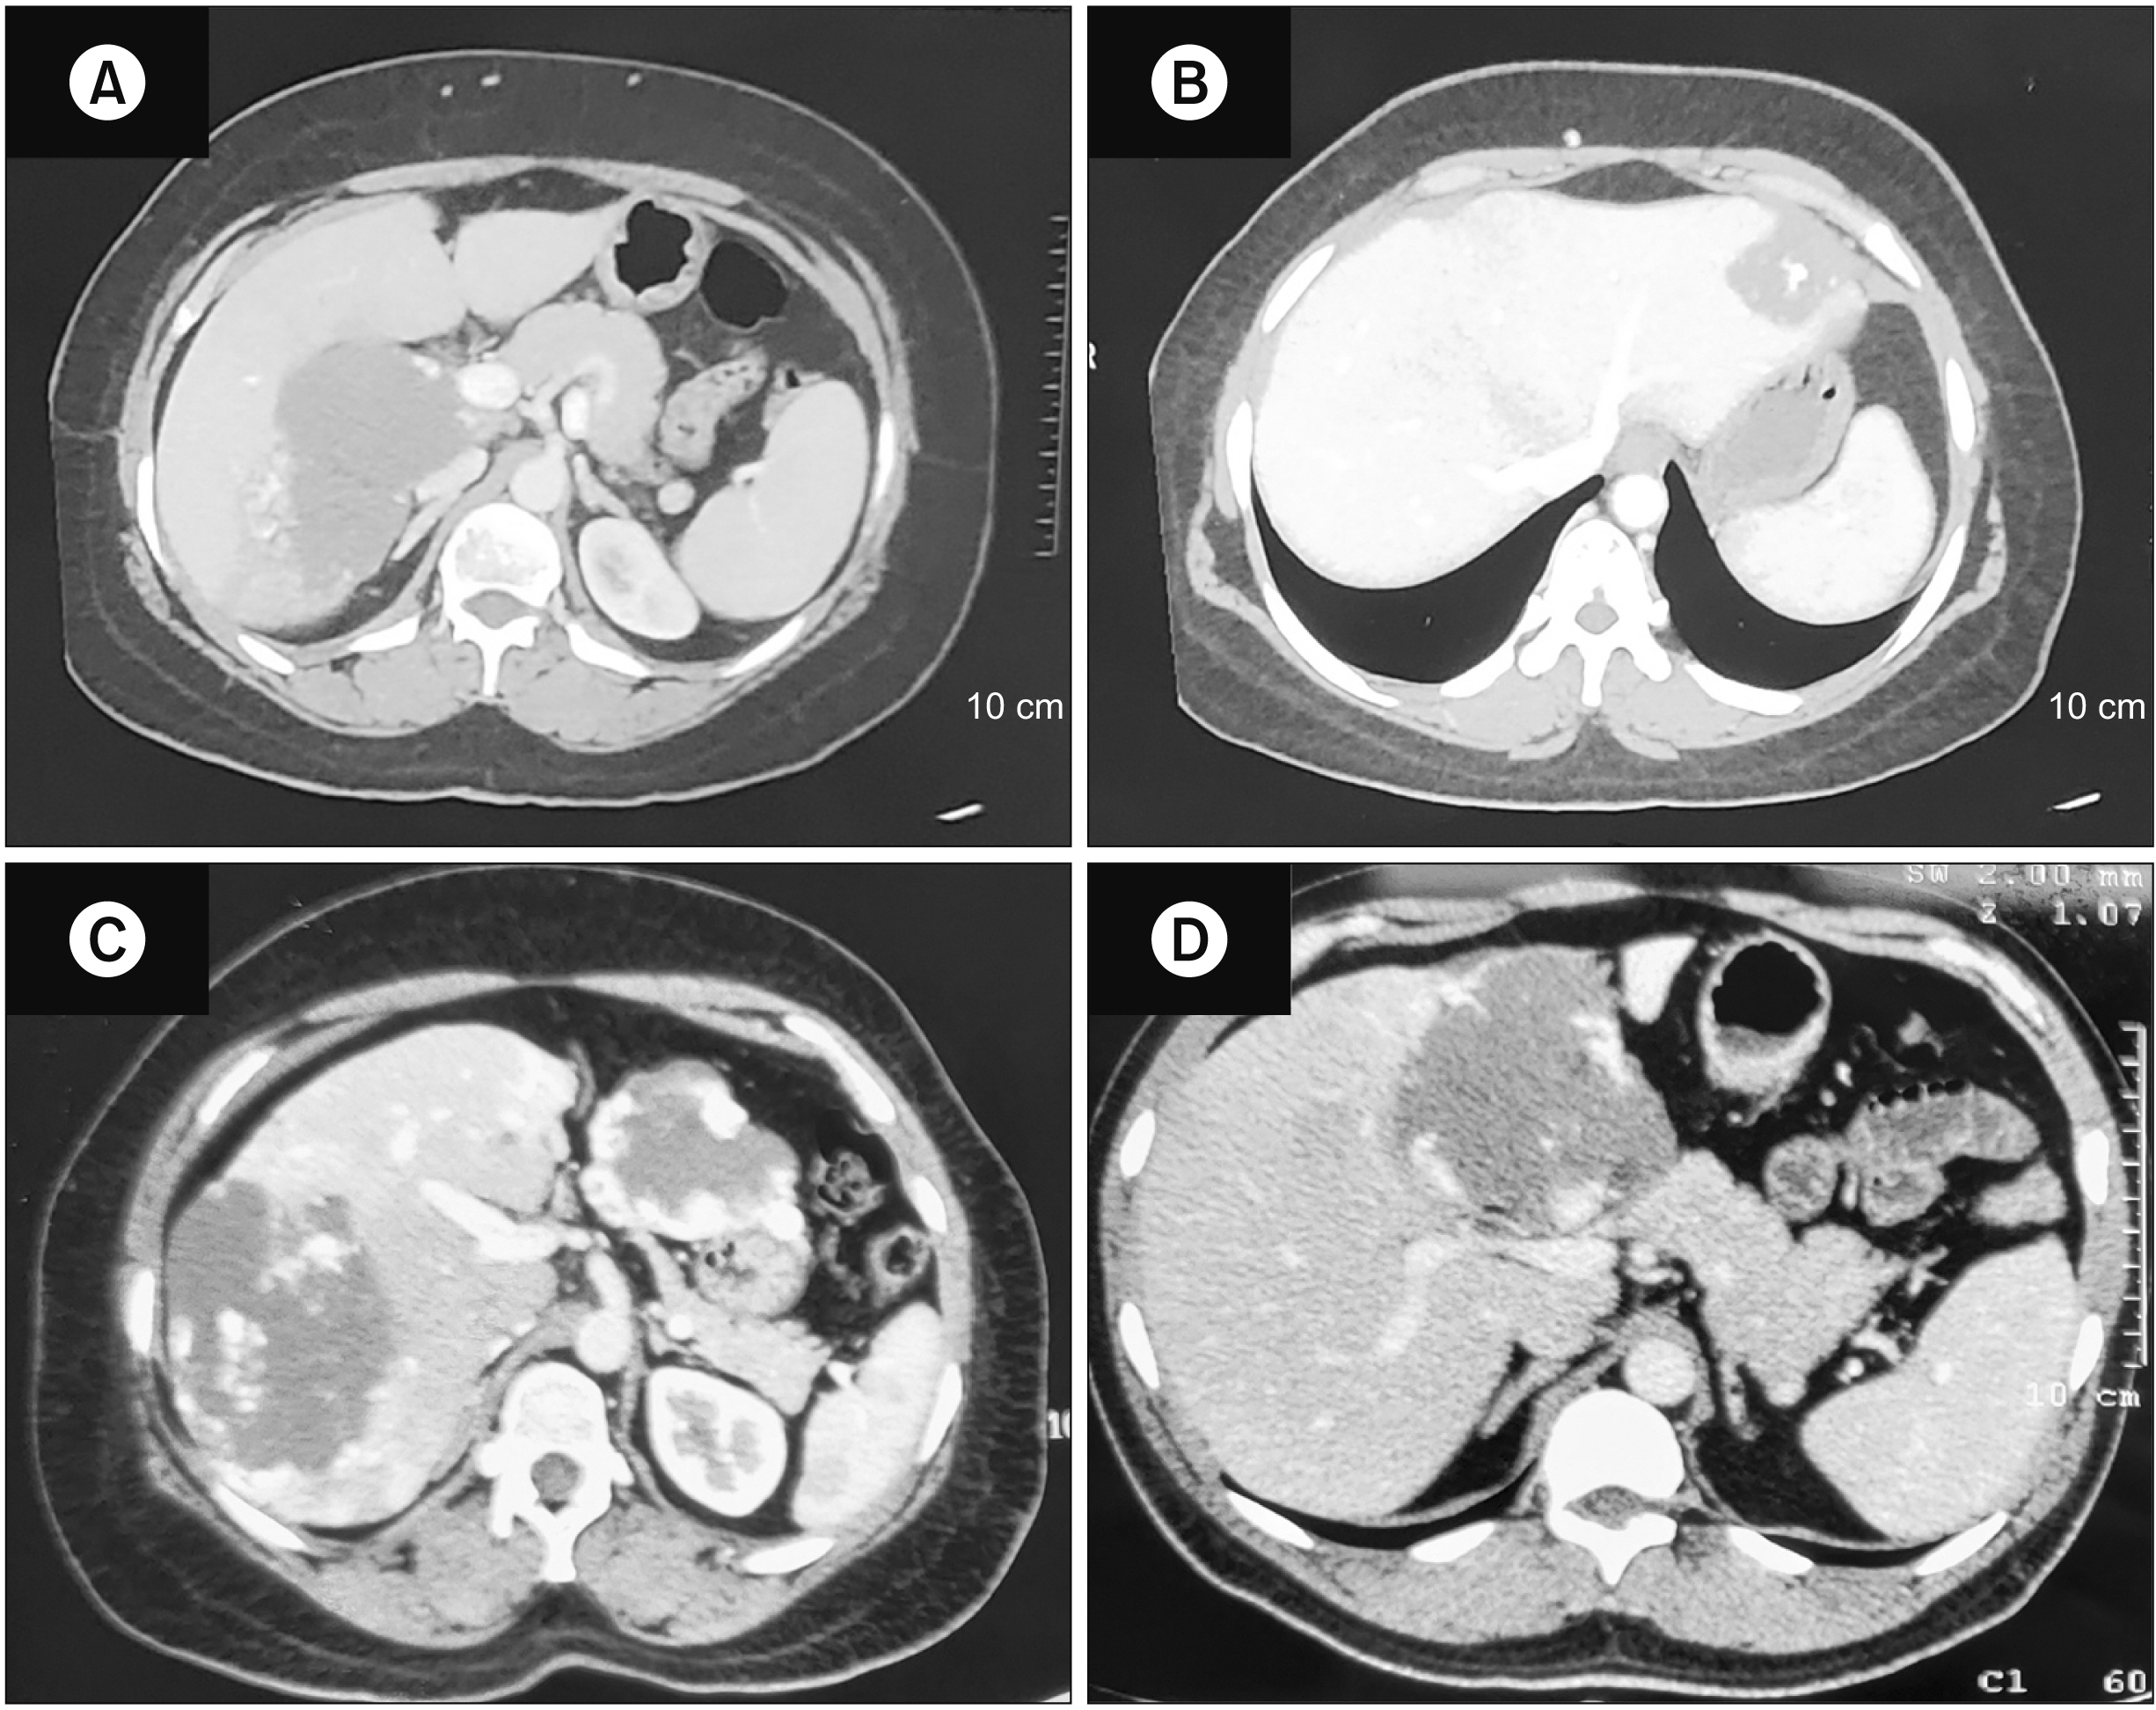

Figure